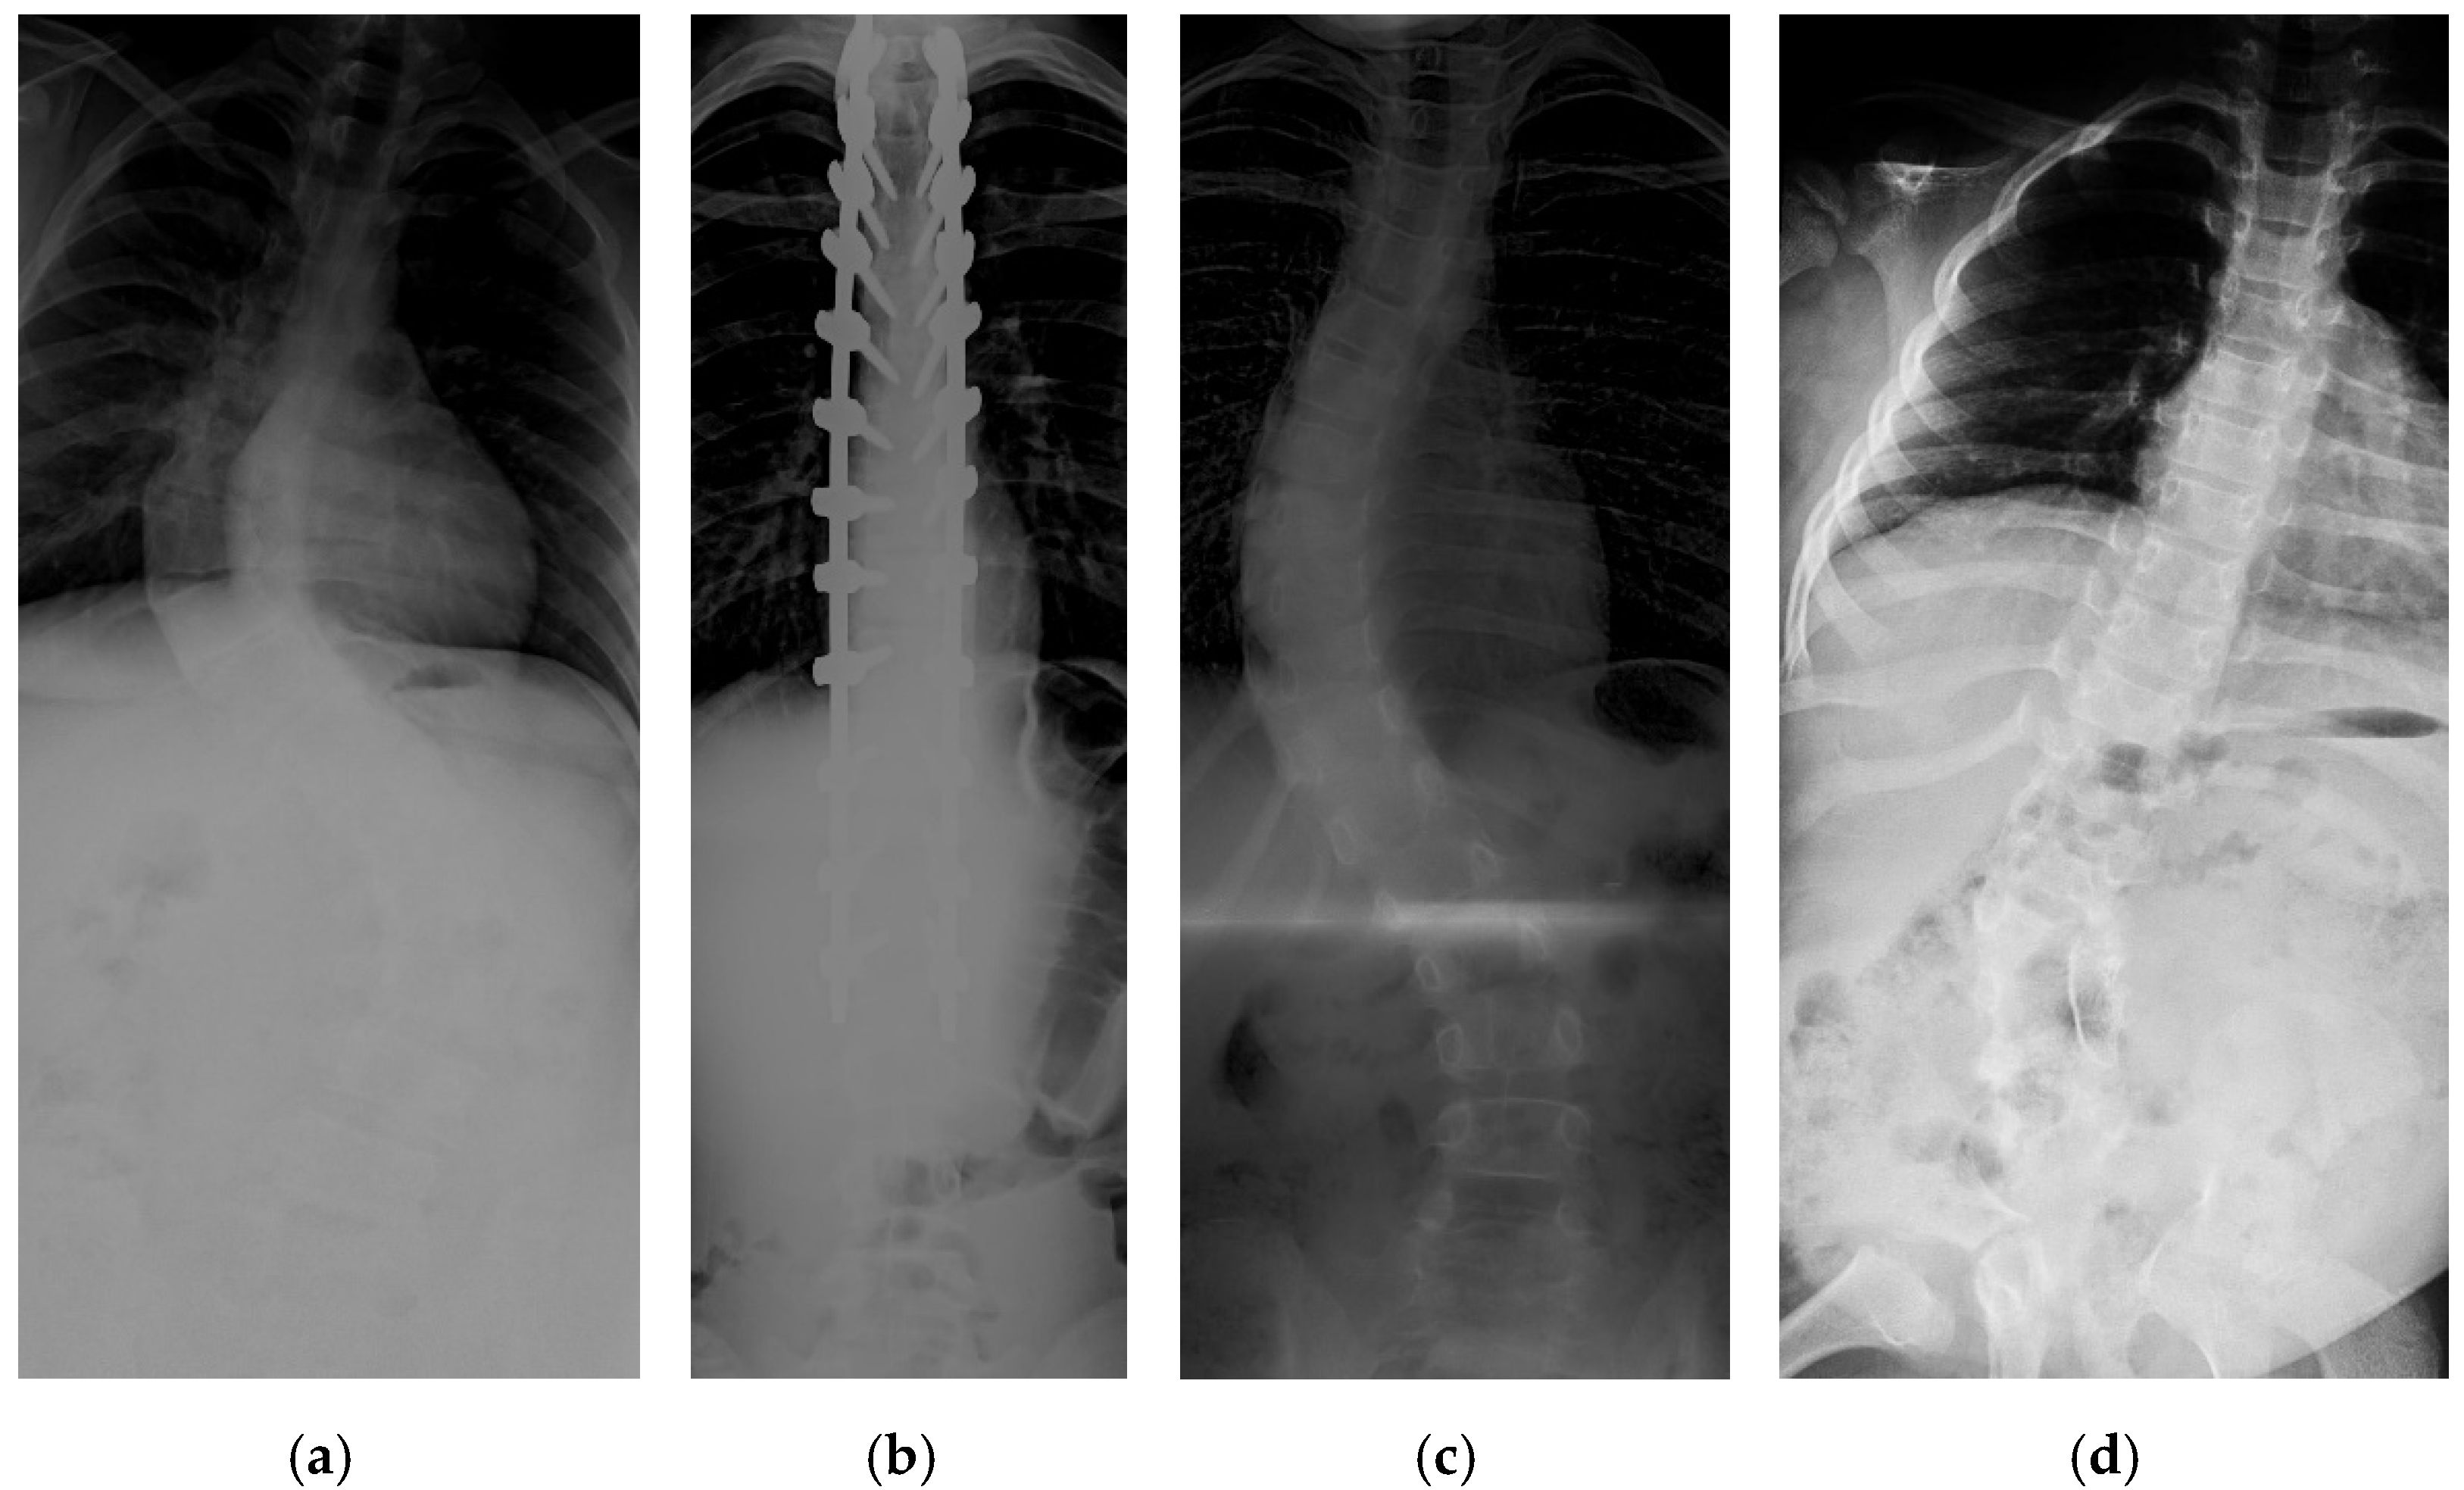

Figure 1.

Examples of some challenging image conditions: (a) Image with noise; (b) high contrast image; (c) low light image; (d) spine with high CA.

The collection and labeling of spinal images were performed by the public AASCE MICCAI 2019 anterior-posterior X-ray images dataset [18]. The input images vary in size from 359 × 973 to 1427 × 3755. Some challenging images can be handled due to our large number of training image conditions, which include images with different noise, contrast, lighting conditions, and spines with high CA, as shown in Figure 1. Each image contains 17 vertebrae from the thoracic (upper spine) and lumbar (lower spine) regions. The image input resolution is set to 1024 × 512 for the algorithm development. Each vertebra is located by four corner landmarks. The ground-truth of the 68 landmarks or points in each image is provided by the dataset.